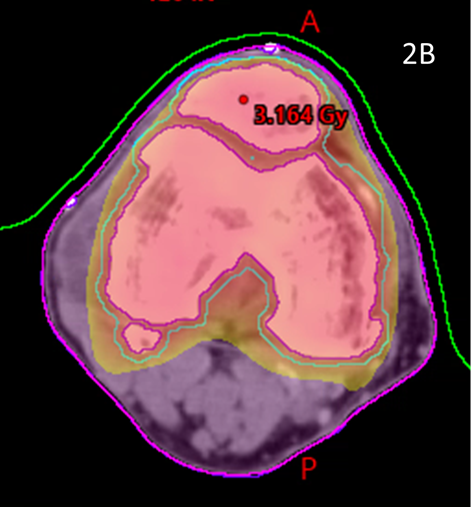

These volumes were then approved by the RO. The target volume was intended to be the joint including synovium with prescription to cover the PTV with 95% of the prescription dose. (Figure 2)

Figure 2 Contouring and dosimetry.

Figure 2A Axial planning CT slice through zero plane of knee in Figure 1A showing PTV (blue volume indicated by white arrow) as 2 mm expansion of CTV which was an auto contour of the bone.

Figure 2B Axial planning CT slice through zero plane showing dosimetry as colour wash set at 2.5Gy level. Notice excellent conformity to PTV and homogeneity within the PTV and sparing of soft tissues that may not have been spared by a 3DCRT approach.

Figure 2C Axial planning CT slice through zero plane of hands in Figure 1B showing PTV (blue volume) as 2 mm expansion of CTV which was an auto contour of the bone.

Figure 2D Axial planning CT slice through zero plane showing dosimetry as colour wash set at 2.5Gy level. Similar to Figure 2B, notice excellent conformity to PTV and homogeneity within the PTV while sparing the palms.